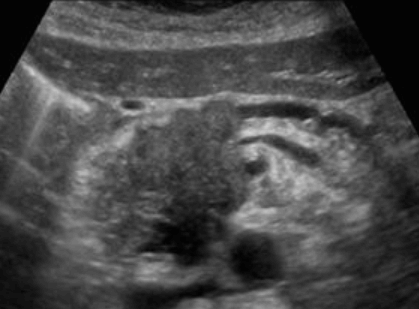

간내담관암(intrahepatic cholagiocarcinoma) ▣ 간문부 담관암(Klatskin's tumor = Hilar cholagiocarcinoma)

- 좌우 간내담관이 갈라지는 간문부에서 발생하는 암이다.

- 담관암의 50%를 차지한다.

- 대부분의 환자는 폐쇄성 황달을 일으킨다.

US finding

- 간내담관은 확장되고 간외담관은 정상이다.

- 담낭은 위축되며, 간외담관은 담즙 흐름이 없는 담관으로 묘출된다.

- 폐쇄된 담관부위에 종양의 윤곽이 보일 수 있으나 초음파상 발견하기 어렵다.